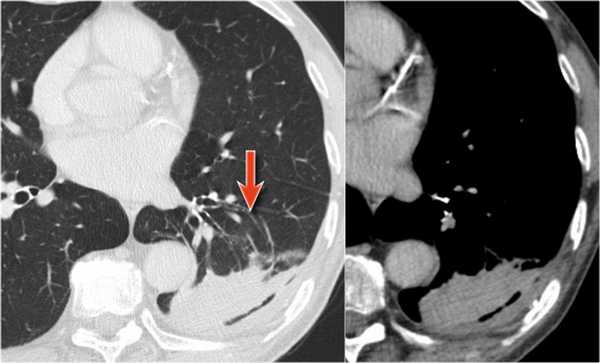

Ателектаз верхней доли левого легкого с типичным симптомом воздушного серпа (Luftsichel sign — luft(air)+sichel(sickle)), обусловленный гипервентиляцией верхнего сегмента нижней доли левого легкого на фоне коллапса верхний доли левого легкого. Гипервентилируемый

сегмент визуализируется на прямой рентгенограмме от дуги аорты до апикальной части легкого.

Симптом воздушного серпа (luft sichel sign) — это симптом, который возможно встретить на рентгенограмме органов грудной полости при ателектазе верхней доли левого легкого.

Изменения на рентгенограмме обусловлены гипервентиляцией верхнего сегмента нижней доли левого легкого, который смещается к сзади и кверху, и тем самым располагается между коллабированной долей легких и средостением. На фронтальной рентгенограмме сегмент визуализируется от дуги аорты до апикальной части левого легкого.

На рентгенограмме представлен тотальный коллапс верхней доли левого легкого. Обратите внимание на высокое стояние левого корня легкого. Спавшаяся верхняя доля левого легкого расположено позади грудины. В данном случае компенсаторная гипервентиляция нижней доли левого легкого повлияло на то, что позиция диафрагмы и средостения в норме.